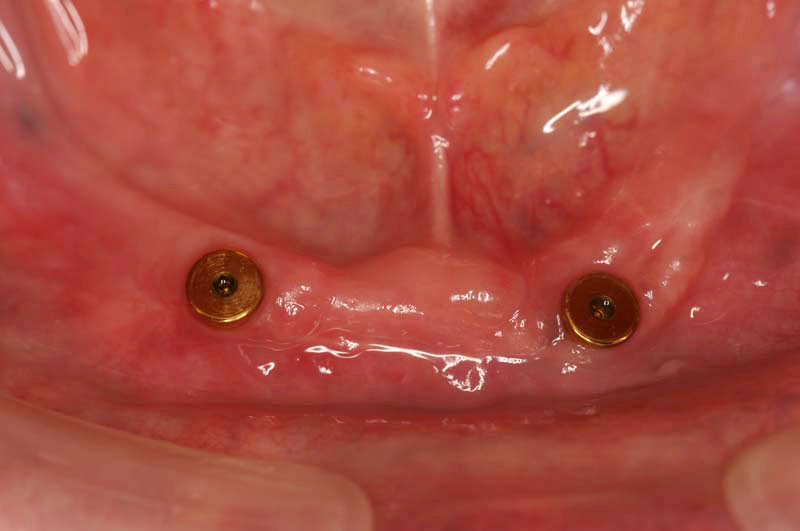

CASE 1 歯の全くない方

歯の全くない方の場合、インプラントを4本いれるとブリッジでつなげて自分の歯のようにすることが可能です。または2本いれて磁石の力で従来の総入れ歯を吸い付かせる方法も可能です。